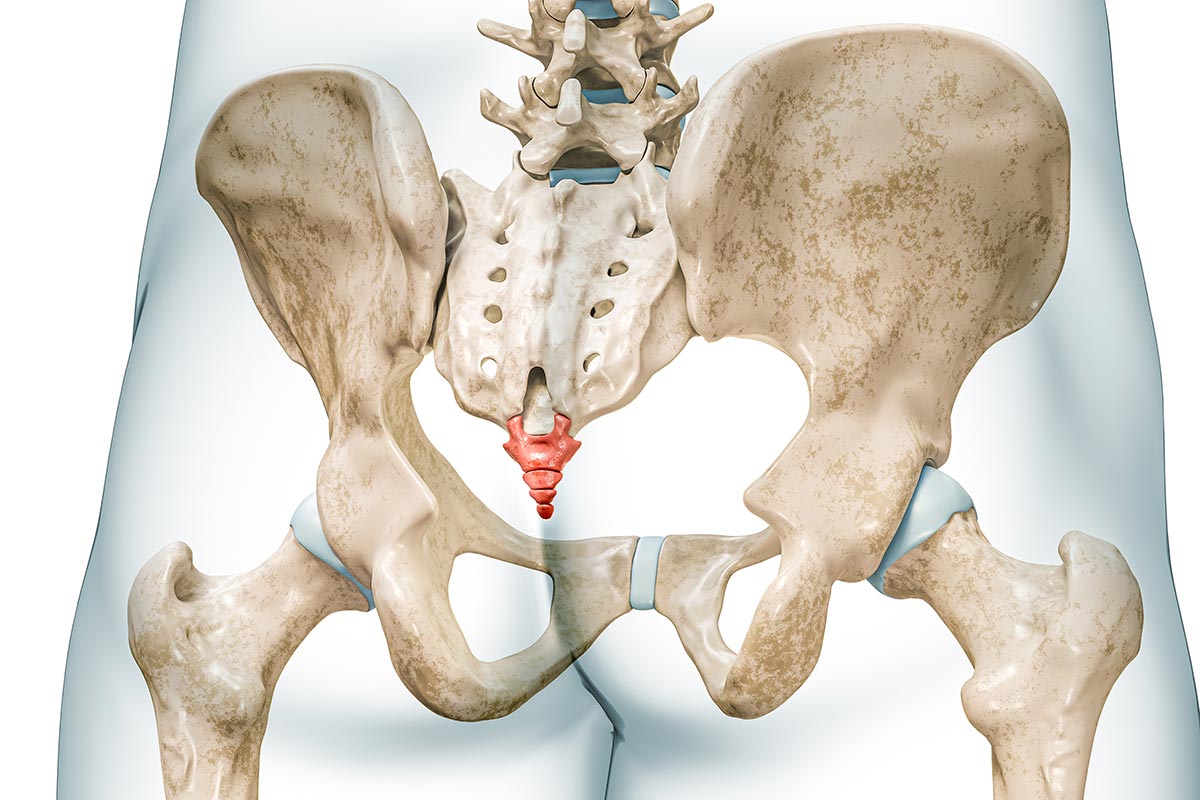

Steißbeinschmerzen (Coccygodynie)

Steißbeinschmerzen, medizinisch als Coccygodynie bezeichnet, sind eine oft sehr belastende und für Betroffene frustrierende Schmerzproblematik. Die Beschwerden entstehen im Bereich des Steißbeins (Os coccygis) und können die Sitzfähigkeit sowie alltägliche Aktivitäten erheblich einschränken.

Typisch sind lokalisierte Schmerzen im Bereich des Steißbeins, die vor allem beim Sitzen, beim Aufstehen aus dem Sitzen oder bei längerer Belastung auftreten. Häufig besteht eine deutliche Druckschmerzhaftigkeit, gelegentlich auch eine Ausstrahlung in den unteren Rücken oder den Beckenbereich. Die Schmerzintensität kann stark variieren und ist oft positions- oder belastungsabhängig.